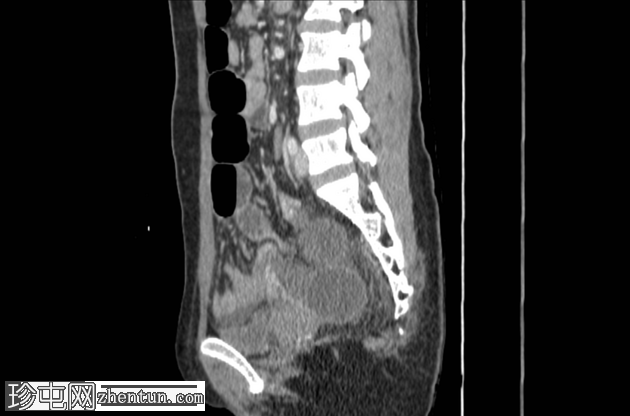

矢状位增强扫描(门静脉期)

小肠袢明显扩张,左侧附件区可见双移行点,远端回肠短段闭袢梗阻,肠颈位于左侧输卵管/左侧子宫血管附近。

肠系膜血管充血,腹盆腔可见游离液体,提示肠系膜充血。

远端回肠袢和结肠已减压。

无肠缺血或穿孔的影像学证据。

CT 检查结果提示左侧附件水平小肠短段闭袢性梗阻。肠段的移行点和形态提示可能存在阔韧带或与左侧附件结构相关的粘连带引起的内疝。

剖腹探查发现一段小肠经左侧子宫阔韧带的小缺损处疝出并发生绞窄。复位绞窄的肠段后,缝合阔韧带缺损。